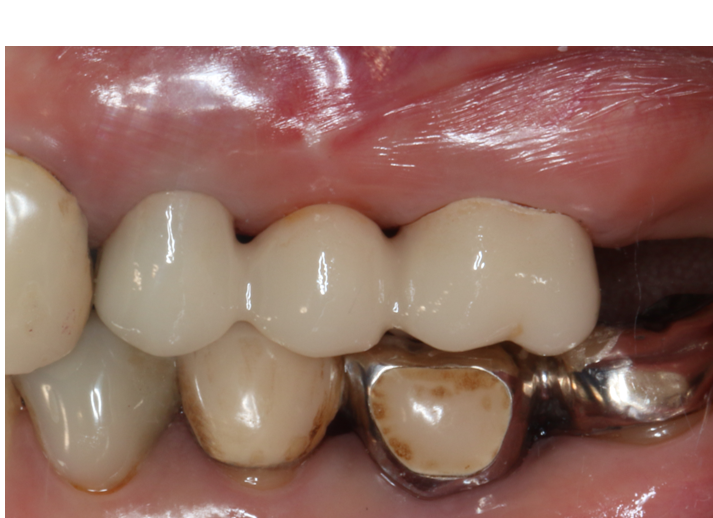

症例2

| 項目 | 詳細 |

|---|---|

| 患者様データ | 50代 女性 |

| 来院時の主訴 | 「左上の歯の周辺から膿が出て臭う。」 |

| 医院の診断 | 虫歯の再発、慢性根尖性歯周炎 |

| 通院期間 | 6ヶ月 |

| 来院回数 | 10回 |

| 治療費 | 580,000円(税抜) 《内訳》 精密感染根管治療80,000円(小臼歯)+100,000円(大臼歯)、ファイバーポストコア20,000円×2、セラミックブリッジ360,000円 |

| リスクと副作用 | ①根管治療歯は長期的には破折するリスク ②メインテナンスが必要 |

| ココがこだわりのポイント☝ |

ラバーダム防湿とマイクロスコープを使用して丁寧に治療を行いました。 再根管治療のため、殺菌性があり歯を補強することのできる根管充填材料を使用しています。 |